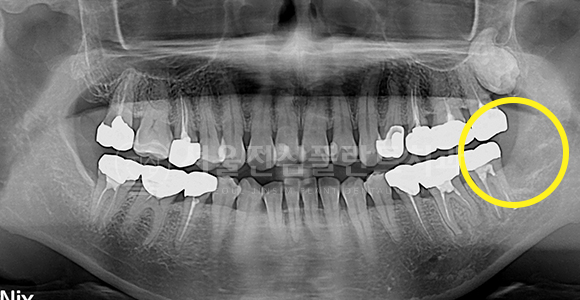

고난이도 매복 사랑니 발치

BEFORE

하악 신경관에 근접한 고난이도 사랑니도 안전하게 발치합니다.